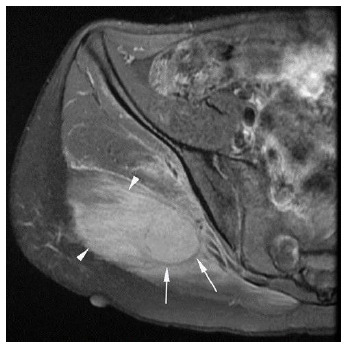

Findings: Palpation of the right buttock indicated a tender mass. Investigation by musculoskeletal ultrasound detected a large hypoechoic lesion. An MRI revealed patterns of calcification that were inconclusive in differentiating between a malignant or benign lesion. Macroscopic and microscopic histological examination, as well as immunohistochemistry, were consistent with myositis ossificans (MO), a non-malignant condition. The patient improved remarkably within three months of treatment with rest, non-steroidal anti-inflammatory drugs (NSAIDs) and extracorporeal shock wave therapy (ESWT).